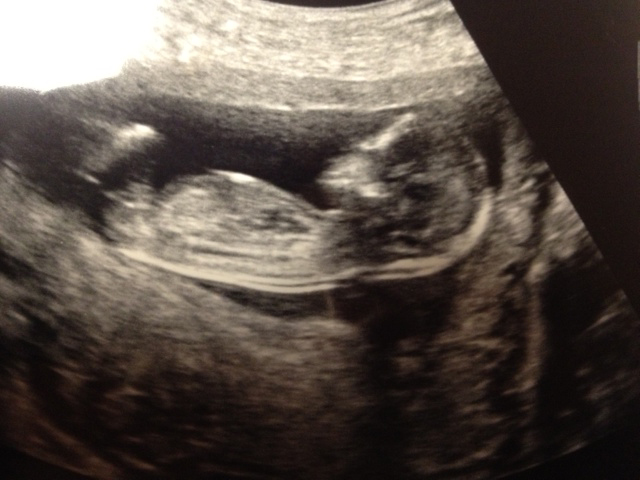

Potty shot at 14w (actually I think it may have been 13+6 or something)

Attachment 2763

Attachment 2764